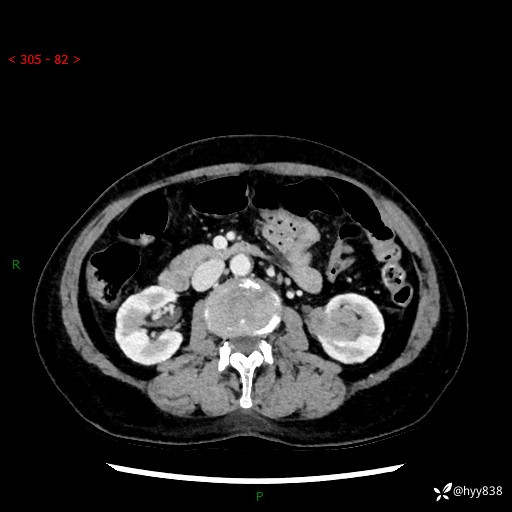

72岁/女,检查发现左肾占位1天。为了满足诊断,常规四期后,又加了延迟期-结果公布~

【患者信息】:72岁/女

【主诉】:检查发现左肾占位1天

【现病史及既往史】:患者于1天前检查发现左肾占位,无畏寒发热,无咳嗽咳痰,无腰腹部疼痛不适,无肉眼血尿、无尿频尿急症状,起病来,患者未行特殊治疗,为求进一步诊治,门诊以"左肾占位"收治入院。 发病来患者精神、饮食、睡眠良好,小便如上,大便正常,体重无明显变化。

【检查】:肾脏CT平扫+增强